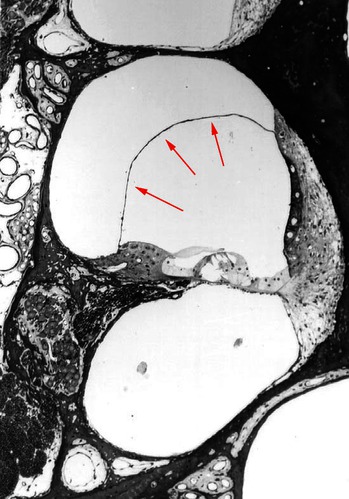

Het slakkenhuis (binnenoor) bestaat uit drie ruimten die gevuld zijn met vloeistof (zie figuur 2 en 3). Het bovenste en onderste deel zijn gevuld met perilymfe. De middelste ruimte is gevuld met endolymfe. In de middelste ruimte bevindt zich het eigenlijke gehoororgaan: het orgaan van Corti. Het vliesje tussen de middelste en bovenste ruimte heet: membraan van Reisner. De middelste ruimte is verbonden met het evenwichtsorgaan. Veranderingen in de de middelste ruimte beïnvloeden daarom zowel het gehoor als het evenwicht.

Bij de ziekte van Menière ontstaat er in de middelste ruimte een overproductie van endolymfe waardoor het membraan van Reisner onder spanning komt te staan en gaat uitpuilen (figuur 4). Waarschijnlijk veroorzaakt dit ook het drukgevoel waar veel patiënten voor een aanval last van hebben.

Als het membraan te veel wordt uitgerekt, zal het scheuren. De endolymfe en de perilymfe worden dan met elkaar vermengd. Hierdoor raken het orgaan van Corti en het evenwichtsorgaan allebei in de war. Dat geeft gehoorverlies, oorsuizen én duizeligheid: een Ménière-aanval. Door de scheur in het membraan verdwijnt de spanning op het membraam. Het membraan is elastisch en neemt daarom vrij snel zijn oude stand weer aan. Het scheurtje geneest met een klein litteken en de beide vloeistoffen krijgen binnen een paar dagen weer hun oorspronkelijke samenstelling. De aanval gaat dan geleidelijk voorbij maar er blijft nog vrij lang een onzeker gevoel bestaan. Hierna ontstaat weer overproductie van endolymfe waardoor weer een nieuwe Ménière-aanval kan ontstaan.